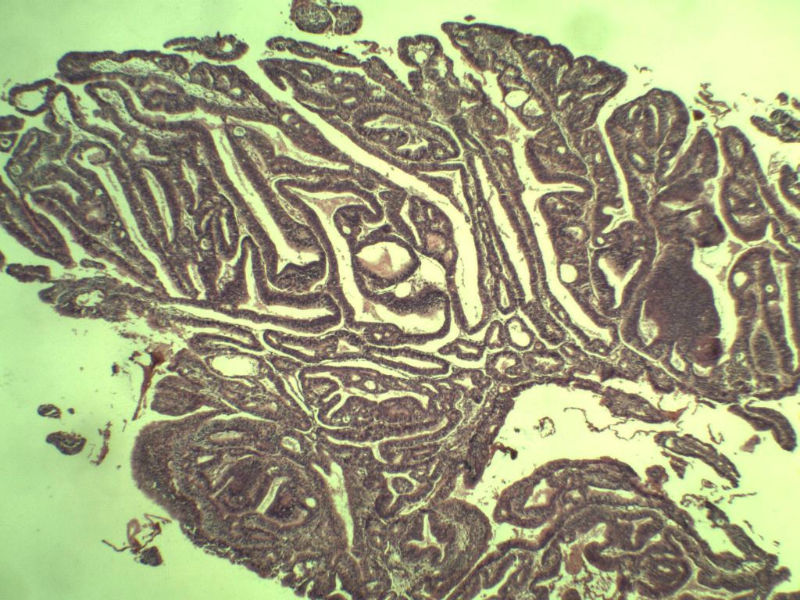

女 32岁 不规则阴道流血 一年  请各位老师看看 谢谢了

遵义医学院附属医院会诊结果    "复杂性增生伴非典型性 "

补充一下病史 病人10个月前因月经不规则行诊刮 诊断非典型性增生  上了曼月乐避孕环(好像是缓慢释放孕激素的那种),         都用激素治疗大半年了 还是这个样子 我还是觉得是癌  只有追踪一下以后病人的情况吧

高分化子宫内膜样癌

非典型复杂性子宫内膜增生,应了解雌孕激素情况。

子宫内膜复杂性非典型性增生,局灶区间质肉芽样(图5)及蜕膜样变,不够癌,建议临床查激素水平并追踪。

从照片看,没看到浸润的地方,我考虑是子宫内膜重度不典型增生。